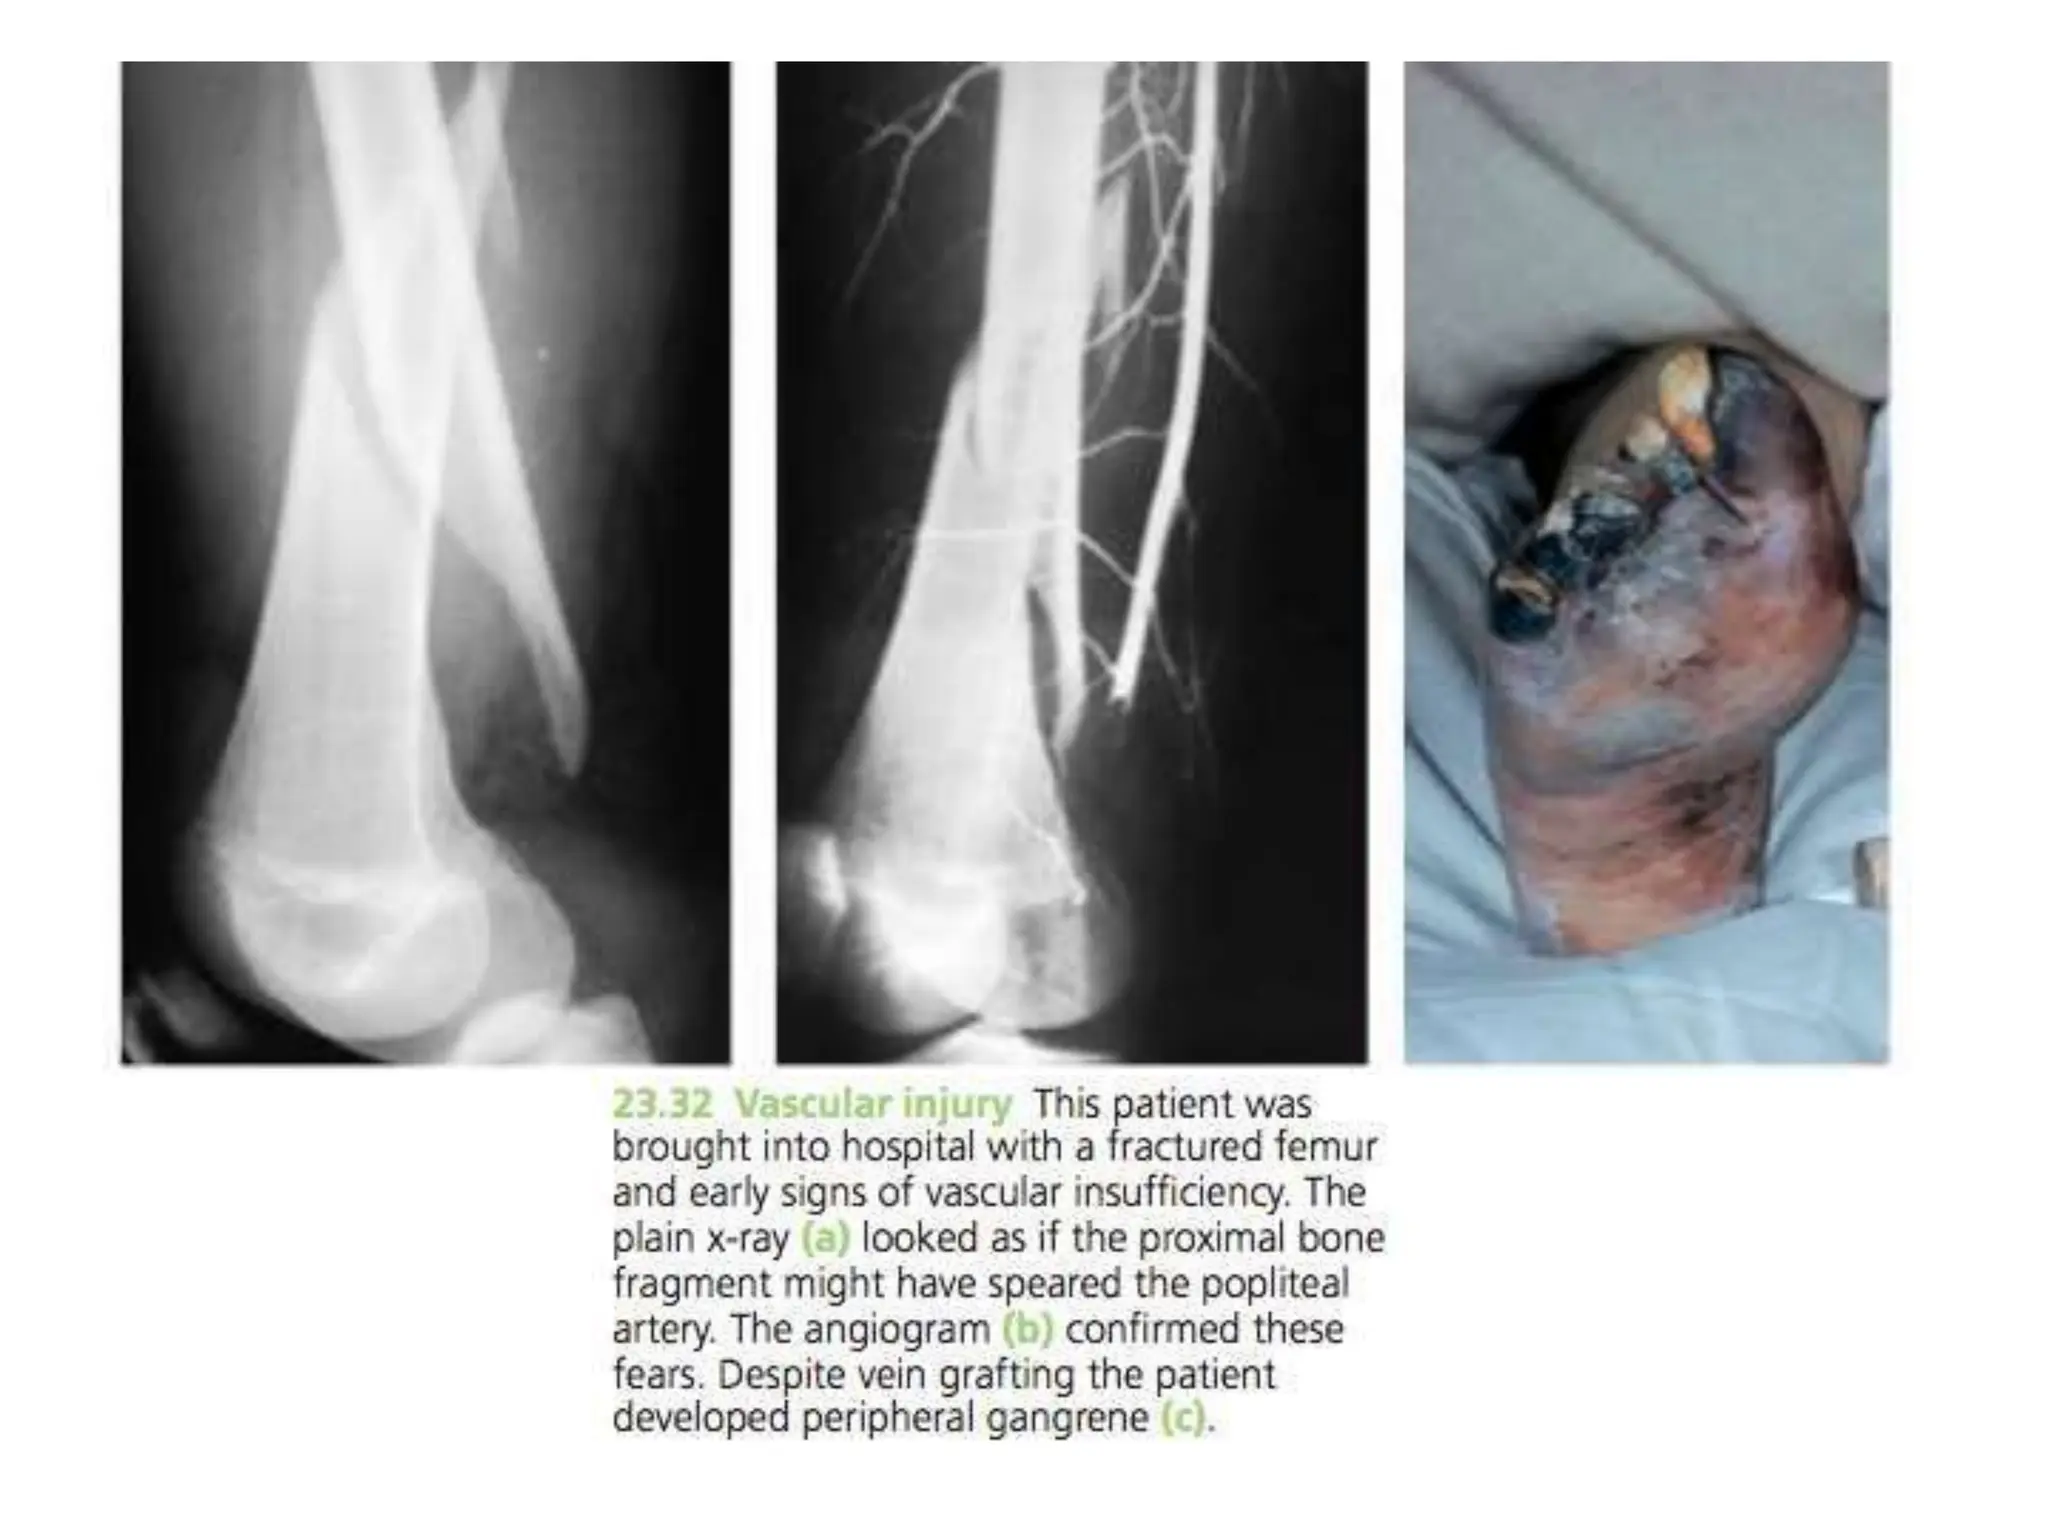

VASCULAR INJURY

Injury Vessel

First rib fracture Subcalvian

Shoulder dislocation Axillary

Humeral supracondylar fracture Brachial

Elbow dislocation Brachial

Pelvic fracture Presacral and internal iliac

Femoral supracondylar fracture Femoral

Knee dislocation Popliteal

Proximal tibial Popliteal or its branches

Clinical features

• Paraesthesia or numbness

• Injured limb is cold and pale or slightly

cyanosed

• Weak or absent pulse

Treament

• All bandages and splints should be remove

• Fractures re-x-rayed and if artery is being

compressed prompt reduction is required

• Circulation reassessed repeatedly over the

next half hour

• If no improvement, vessels must be explored

by operation with pre or peroperative

angiography

• Cut vessel can be sutured, or a segment may

be replaced by a vein graft, if it is thrombosed,

endarterectomy may restore blood flow

• If vessel repair is done, stable fixation is a

must and fracture should be fixed internally